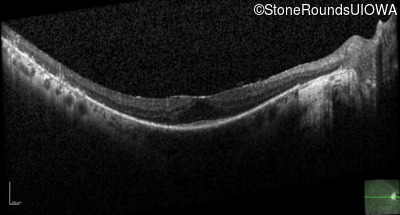

Optical Coherence Tomography - Left - 20/20 -2

Exemplar / OCT Stack

OCT Stack